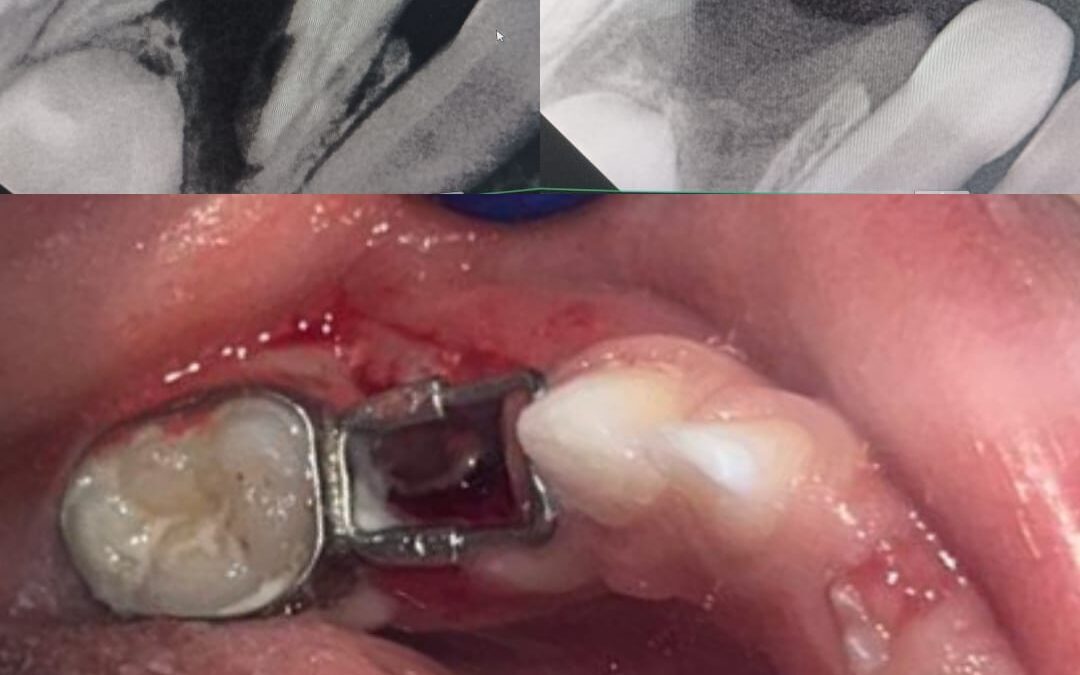

1. Fixed Space Maintainer

This type is cemented to adjacent teeth and cannot be removed by the child.

Common types include:

- Band and loop

- Crown and loop

- Lingual holding arch

These are most commonly used in pediatric dentistry.

How Is a Tooth Space Maintainer Placed?

The procedure is simple and painless.

Step-by-step process:

- Dental examination and X-ray

- Measurement of space

- Custom fabrication

- Fitting and cementation

The entire procedure is comfortable and completed in minimal visits.